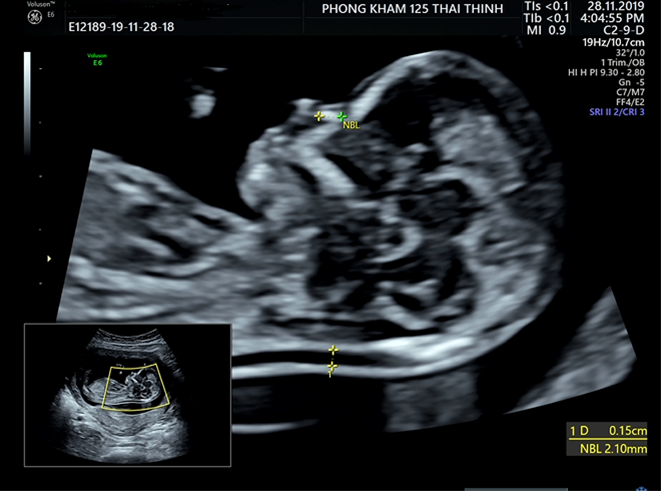

Giai đoạn 2: Đo trong các quý sau của thai kỳ

- Trong các lần siêu âm tiếp theo, các mẹ bầu đều được bác sĩ sẽ thực hiện đo xương mũi của thai. Trong giai đoạn này chiều dài xương mũi khá quan trọng vì không có xương mũi hay xương mũi ngắn đều làm tăng nguy cơ mắc bệnh Down ở thai nhi.

- Các nhà nghiên cứu cũng chỉ ra rằng, nếu thai thi không có xương mũi trong siêu âm quý I (giai đoạn 12 tuần), mà đến các quý tiếp theo thai nhi vẫn không có xương mũi hoặc xương mũi ngắn thì nguy cơ mắc bệnh Down sẽ tăng lên 83 lần.

- Với những thai nhi không có xương mũi hay xương mũi ngắn ở những tuần thai này kèm theo xét nghiệm sàng lọc (Double test, Triple test, NIPT) có kết quả nguy cơ cơ sẽ được chỉ định chọc ối xác định thai nhi có mắc bệnh Down hay không.

| 19 - 20 | 5.0 - 7.0 mm (trung bình 6.75mm) | Số liệu ở thai nhi Việt Nam từ 19- 26 tuần |

| 23 - 26 | 6.5 - 8.0 mm | Tăng trưởng theo tuổi thai |